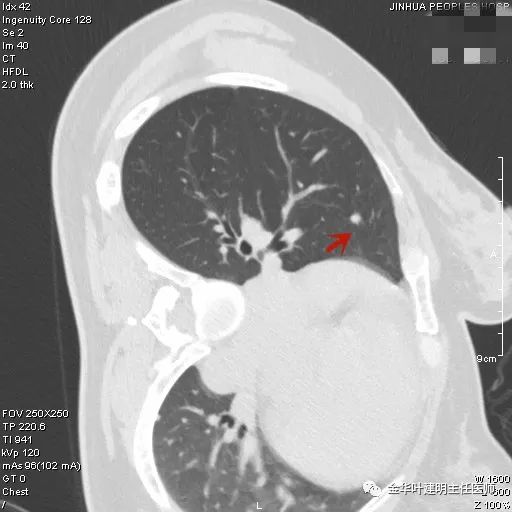

上图示结核。我们发现其有明显的卫星灶,如绿色箭头所示,主病灶处也是周边有模糊区域,病灶整体密度较为均匀(肿瘤容易生长不均致密度欠均匀,显杂乱)。